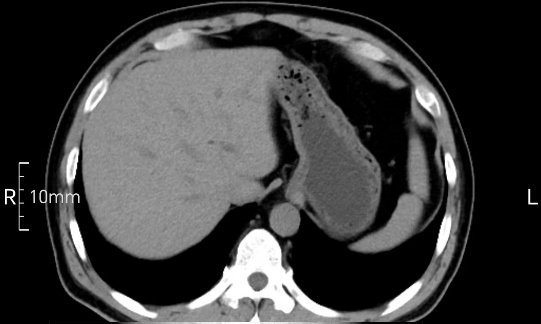

看看下面三幅便知遵醫(yī)囑的重要性。

沒禁食,胃內(nèi)全是食物,導(dǎo)致胃壁顯示不清。

禁食但檢查前沒有喝飽,胃未能漲開,胃壁觀察效果不佳。

完美禁食且喝飽飽,胃壁完美展現(xiàn)。